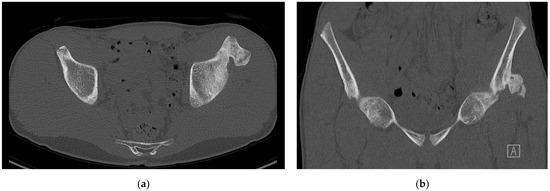

| 1 | 12 | Male | R | None | Kicking a ball | X | 5 mm | NA |

| 2 | 13 | Male | R | None | Kicking a ball | X/CT | 15 mm | 3 |

| 3 | 13 | Male | R | None | Kicking a ball | X/US | 0 mm | 2 |

| 4 | 13 | Male | L + R | Yes | No trauma | X | 0 mm | Unknown * |

| 5 | 15 | Male | R | None | Kicking a ball | X | 8 mm | 2 |

| 6 | 16 | Male | L | None | Fall on knee | X/MRI | 10 mm | 3 |

| 7 | 17 | Male | L | Yes | Jump | X/CT | 10 mm | 3 |